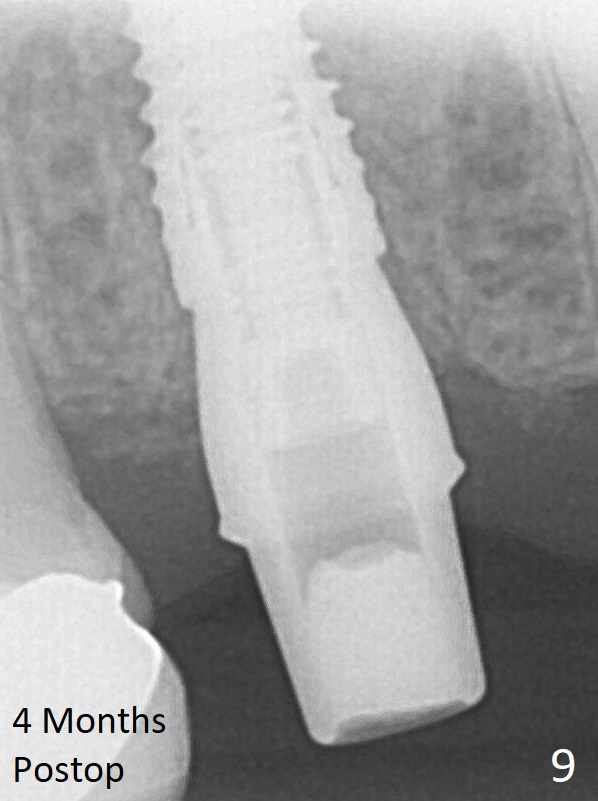

Although the provisional easily dislodges in spite of remake, the implant seems osteointegrated with decreased space 4 months postop (Fig.9).  The gingiva is healthy, although it covers the abutment margin partially.  Gingivectomy appears necessary for impression.